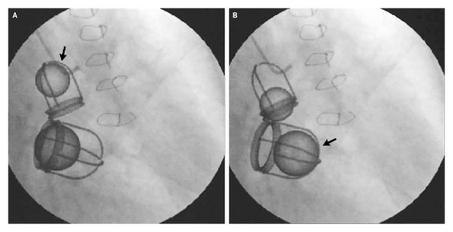

Канал от начинающего кардиолога, на котором выкладывают интересные медицинские иллюстрации, описывают редкие заболевания, а также рассказывают про экспериментальные методы лечения и диагностики. Обратная связь - @DavyJones_bot